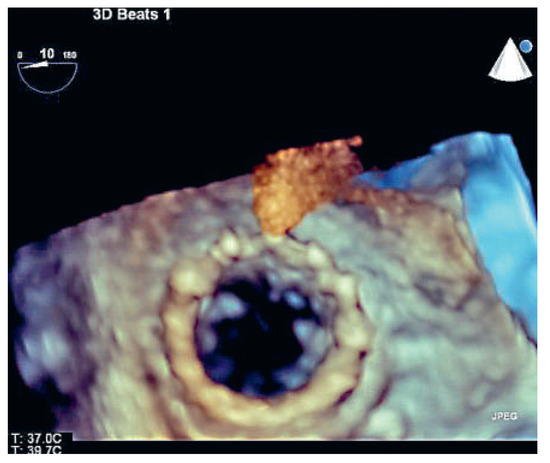

A 41-year-old women with Ebstein’s anomaly required tricuspid valve replacement six years ago. At that time a biological prosthesis was implanted. The tricuspid valve prosthesis became severely stenotic within five years. Instead of re-do surgery, th...